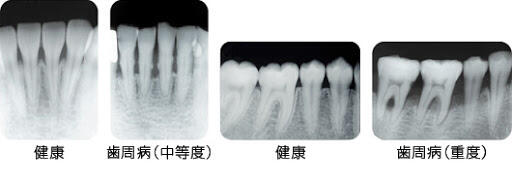

また、エックス線写真により、骨の状態や、歯石の付着状況などがわかります。

もう1つは「歯周病」です。歯周病とは、歯周病菌が歯と歯ぐきのすき間から侵入すると歯ぐきが炎症を起こし、「歯肉炎」になります。これが進行すると歯を支える骨が破壊されて歯周炎(歯周病)になり、さらに放置すると炎症が広がり、歯がグラグラして最終的には抜けてなくなってしまいます。

歯周病の怖いところは、症状がほとんどないということです。

虫歯とは異なり、痛みなどの自覚症状がないため、歯がグラグラするなどの症状で歯科医院を受診した時はかなり重症化しているのです。